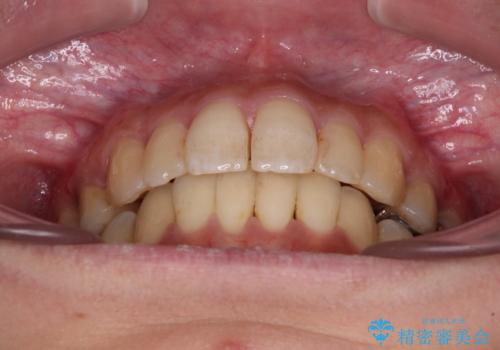

後戻りで突出した前歯をインビザラインで解消

舌の突出癖がなかなか改善できず、IPRによる前歯の隙間が閉じきらずに、予定よりも長い治療期間となりました。

口元の突出感を改善するにあたり、抜歯矯正は行うことができないため、奥歯の後方移動とIPR(歯と歯の間を削る)により達成することとしました。

再度後戻りしたときに対応しやすいよう、インビザラインにて矯正治療を行うこととしました。